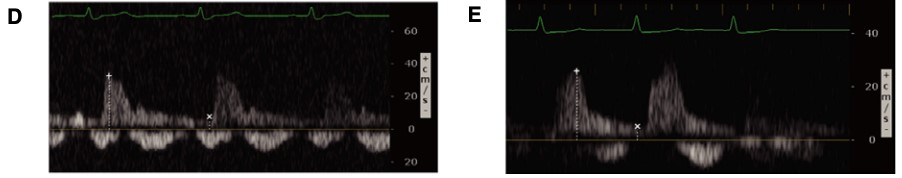

Figure 6. Abnormal hepatic vein Doppler6

(Reproduced with permission)

A: Hepatic flow with S<D wave

B: S wave with reversal

As we go past the hepatic sinusoids, into the portal venous system, the venous flow loses much of its pulsatility and instead maintains a more constant blood flow at normal levels of venous return. The normal portal venous waveform is continuous, as seen in Figure 3, and represents the flow of blood as it is buffered from the hepatic sinusoids. This unique aspect of the portal venous flow makes it more specific for increased venous congestion than measurement of the other veins, as it takes a greater amount of venous congestion to cause pulsatility in the portal vein. As venous congestion worsens, the portal vein will exhibit an increasing variation in the flow as the right atrial pressures increases and the hepatic sinusoids, which help regulate that flow, fail to compensate. This abnormal portal venous pulsatility is seen in Figure 7. As such, the portal vein waveform provides vital information about the ability of the liver itself to regulate venous flow and pulsatility.

Figure 7. Abnormal portal vein Doppler (pulsatile)

(Author's Own Image)

Abnormal portal venous pulsatility